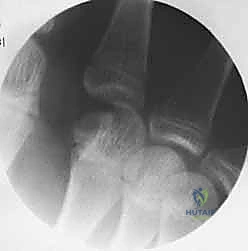

- الأشعة السينية (X-rays): يتم أخذ صور من زوايا متعددة (أمامية خلفية، جانبية، ومائلة) لتحديد موقع الكسر، نوعه (عرضي، حلزوني، مائل، متفتت)، ودرجة التزوي (Angulation).

خطوات التثبيت الجراحي - توثيق بصري (Intraoperative Imaging)

يحرص الدكتور هطيف على توثيق خطوات العمل الجراحي لضمان أعلى مستويات الدقة. نستعرض هنا مجموعة من الصور من داخل غرفة العمليات توضح مدى تعقيد ودقة هذه الجراحات:

معرض الصور الشعاعية: تقييم النتائج الجراحية (Post-Op X-rays)

النجاح الحقيقي يُقاس بالاستعادة المثالية للشكل التشريحي للعظم. توضح هذه الصور الشعاعية بعد الجراحة الدقة المتناهية في إعادة محاذاة العظام وتثبيتها.

التثبيت المحكم يسمح بالشفاء العظمي الأولي (Primary Bone Healing) دون تكوين كتلة عظمية كبيرة (Callus) قد تعيق حركة الأوتار المنزلقة فوقها.